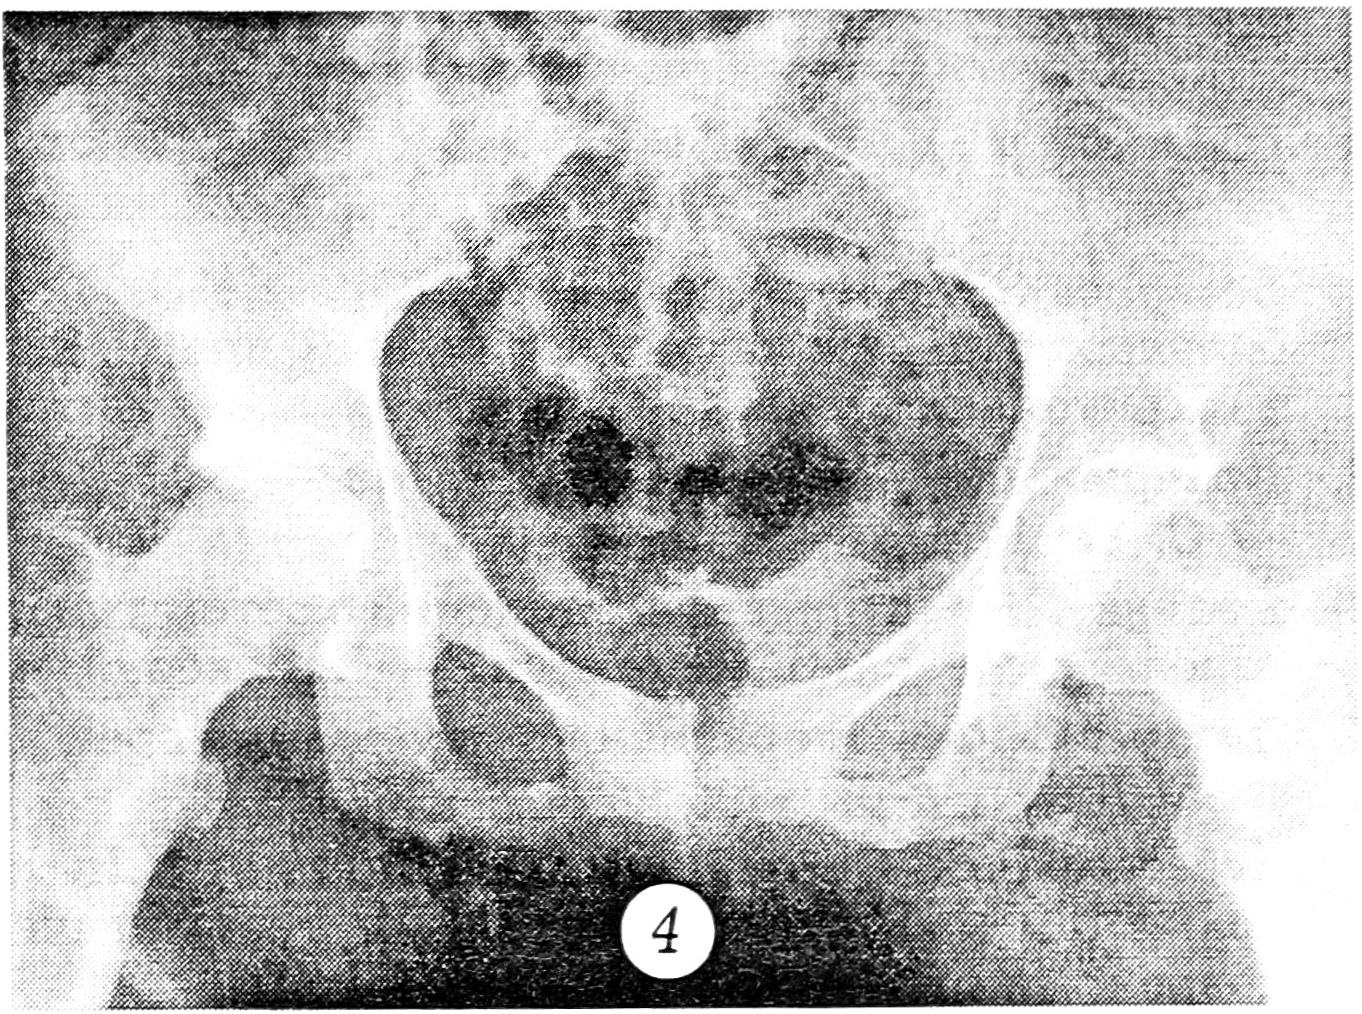

Больной Г., 36 лет, 27.02.95, находясь за рулем автомобиля, попал в автоаварию. Доставлен в больницу по месту получения травмы. При поступлении поставлен диагноз: закрытый вывих левого бедра, перелом вертлужной впадины. Предпринята попытка вправления бедра. После улучшения состояния больного он 1.03 переведен в клинику травматологии ЦИТО. При поступлении проведена рентгенография таза в стандартной переднезадней и запирательной проекциях (рис. 2). Выявлен оскольчатый перелом задневерхнего отдела вертлужной впадины, заподозрено наличие внутрисуставных отломков. С целью уточнения диагноза проведена компьютерная томография тазобедренного сустава. Подтвержден оскольчатый перелом задневерхнего отдела левой вертлужной впадины и, главное, в полости левого тазобедренного сустава выявлены свободный костный фрагмент кортикальной плотности, расположенный в центральном отделе впадины, и несколько более мелких свободных внутрисуставных тел (рис. 3). С учетом характера перелома и внутрисуставной интерпозиции отломков больному 15.03 произведена операция. При ревизии левого тазобедренного сустава в области крыши вертлужной впадины обнаружен фрагмент размером 4,5×5,0×1,5 см с участками хрящевого покрытия и фиброзной губы, смещенный краниально и ротированный кнаружи. После выведения головки бедра из впадины в суставе обнаружены костный фрагмент размером 2,5×1,0×0,8 см из губчатой и компактной ткани и два кортикальных чешуеобразных фрагмента размером 0,7 и 0,5 см. Все костные фрагменты удалены из полости сустава. Сустав промыт. Головка бедра вправлена. Произведена репозиция заднего края вертлужной впадины, фрагмент фиксирован двумя винтами с шайбами. Движения в суставе в полном объеме. Остеосинтез стабильный. Заживление раны первичное. Отдаленный результат хороший.

Рис. 2. Рентгенограммы больного Г. в стандартной переднезадней (а) и запирательной (б) проекциях.